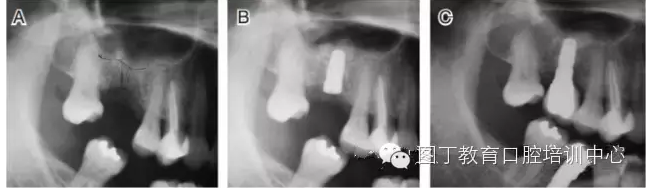

病例2 骨質(zhì)較少(圖4)

圖4